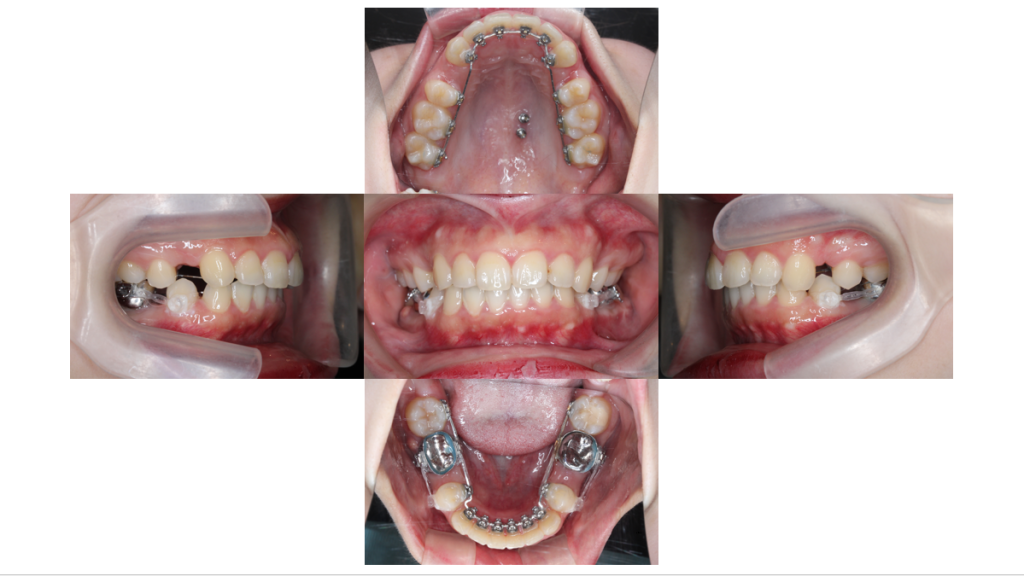

初診

上顎前突・裏側矯正の症例治療開始前の口腔内